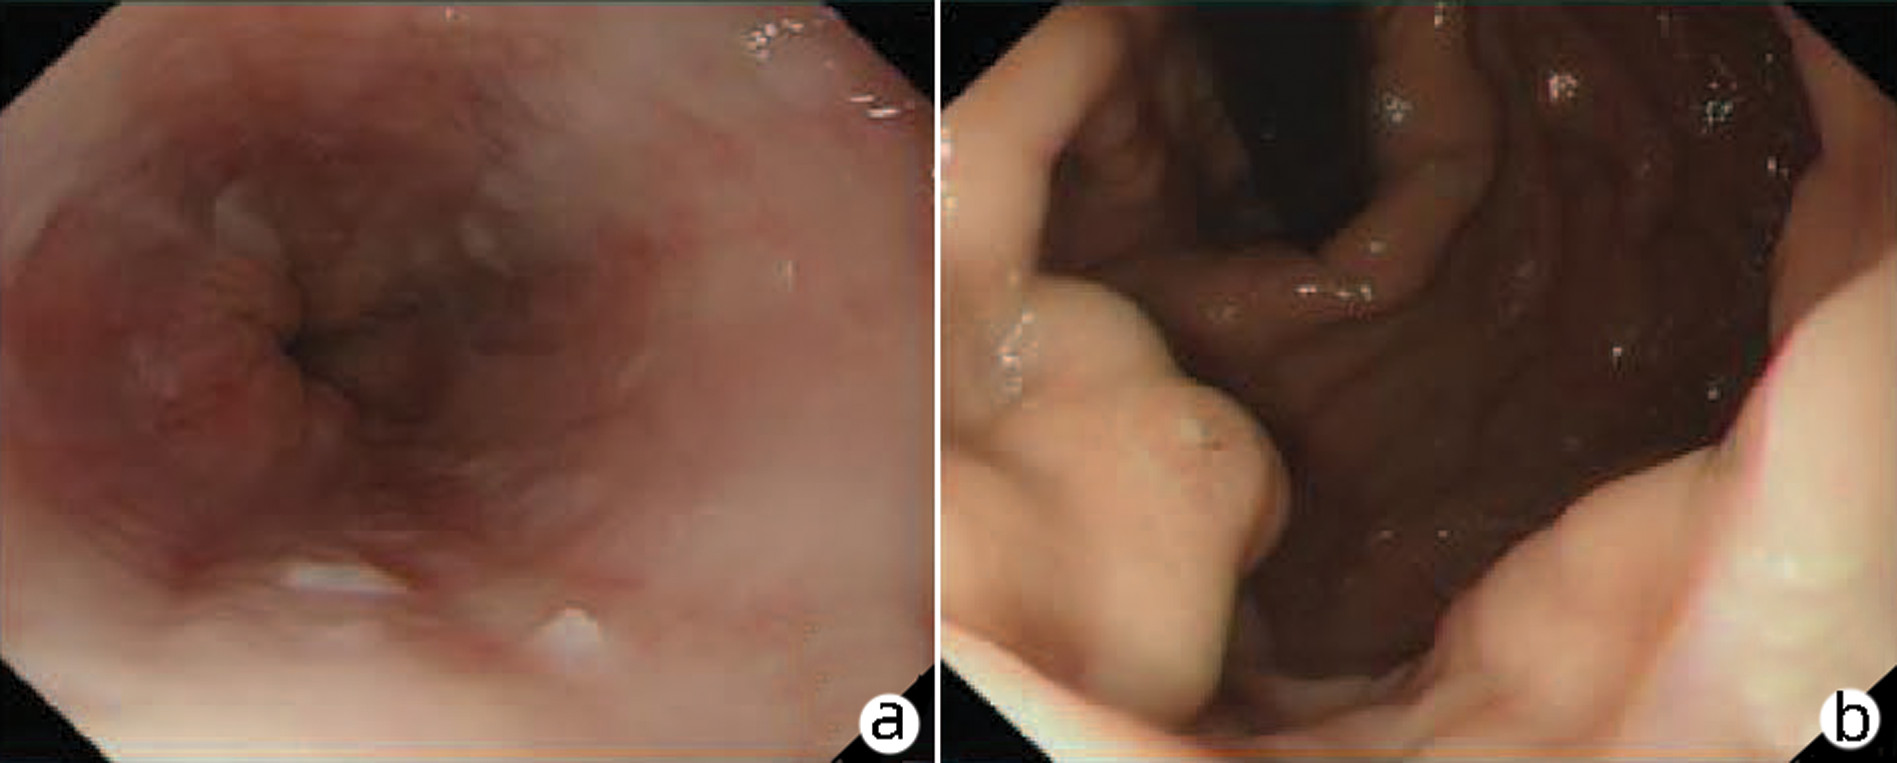

多学科联合诊疗原发性肝脏神经内分泌瘤1例报告

赵凯越, 严哲, 黄缘

2023, 39(6): 1411-1413. DOI: 10.3969/j.issn.1001-5256.2023.06.024

摘要(795) HTML (186) PDF (2153KB)(63)

摘要: